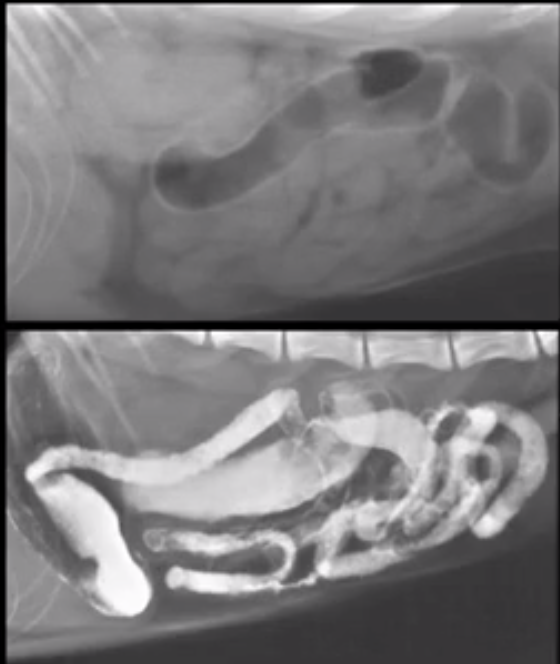

What does this image show?

Mass in lumen

Intussecption - long filling defect with contrast around it

Duodenal mucosal changes due to pancreatitis

Does this kitten have a complete obstruction? Images taken immediately and 20 mins later.

20 mins later contrast can be seen in rectum so not an obstruction